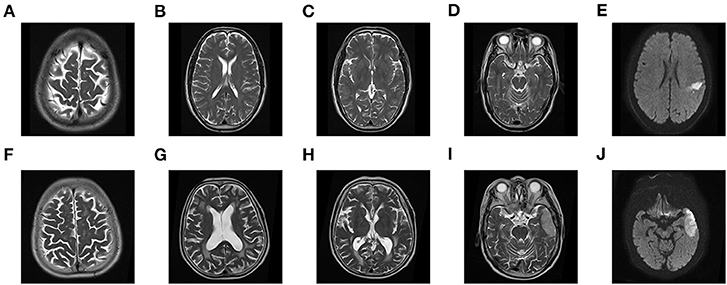

A total of 205 patients met all eligibility criteria and were retained for analyses. 57 (27.8%) patients were diagnosed with SAP, and 40 (19.5%) developed poor outcomes. The variables of the patients were shown in Table 1. During their admission, three individuals died of neurological events, two of whom acquired SAP, accounting for 3.5 per cent of SAP patients. The group with SAP had a higher NIHSS score and A2DS2 score and was older than the non-SAP group (all P < 0.05). In addition, patients with a previous stroke, coronary artery disease, dysphagia and poor consciousness status had an increased probability of SAP (all P < 0.05). There were differences in some neuroimaging findings, such as multiple lobes involved, core infarct volume and brain atrophy score (all P < 0.05). The group with SAP had more severe brain atrophy and larger lesions than the non-SAP group (Figure 2). However, no significant difference in the other neuroimaging findings of CSVD were noted between the patients with SAP and the controls. In addition, some characteristics of laboratory examination did not differ significantly (all P > 0.05). Higher absolute counts of white blood cells, neutrophils, and monocytes, NLR and fasting plasma glucose levels were significantly more likely in those who went on to develop SAP. No significant difference in the treatment methods were noted between the two groups (P = 0.094), except for mechanical ventilation. Among the 205 patients, 17 (11.5%) non-SAP patients had poor outcomes and 23 (40.4%) SAP patients had poor outcomes at 3 months (P < 0.001).

Figure 2. MR features of brain atrophy and core infarct volume. (A) 68-year-old patient developed non-SAP and good functional outcome (MRS, 0 points) with brain atrophy 0 level (A–D) and core infarct volume 54.6 × 50 ML (E). A 70-year-old patient developed SAP and poor functional outcome (MRS, 5 points) with brain atrophy 2 level (F–I) and core infarct volume 419 × 50 ML (J).